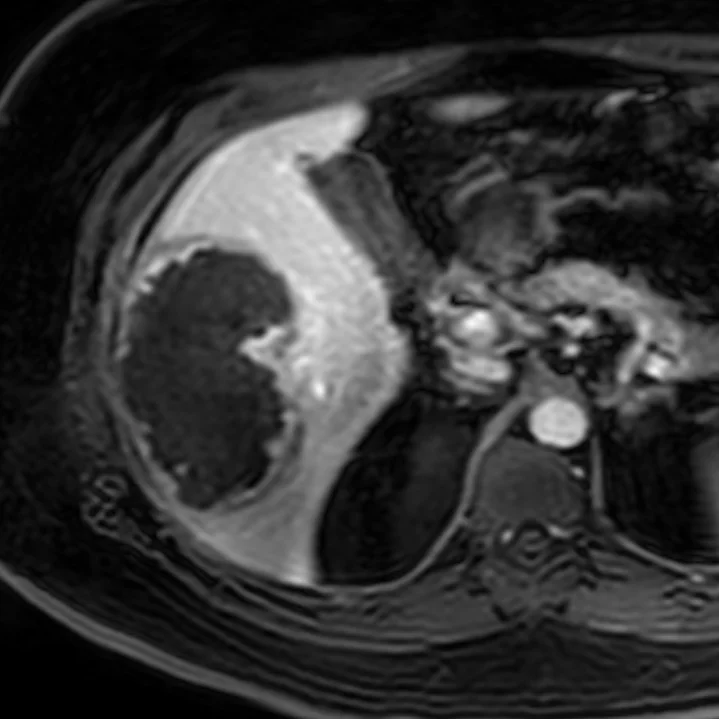

Post-contrast MRI reflects the findings on iodine map